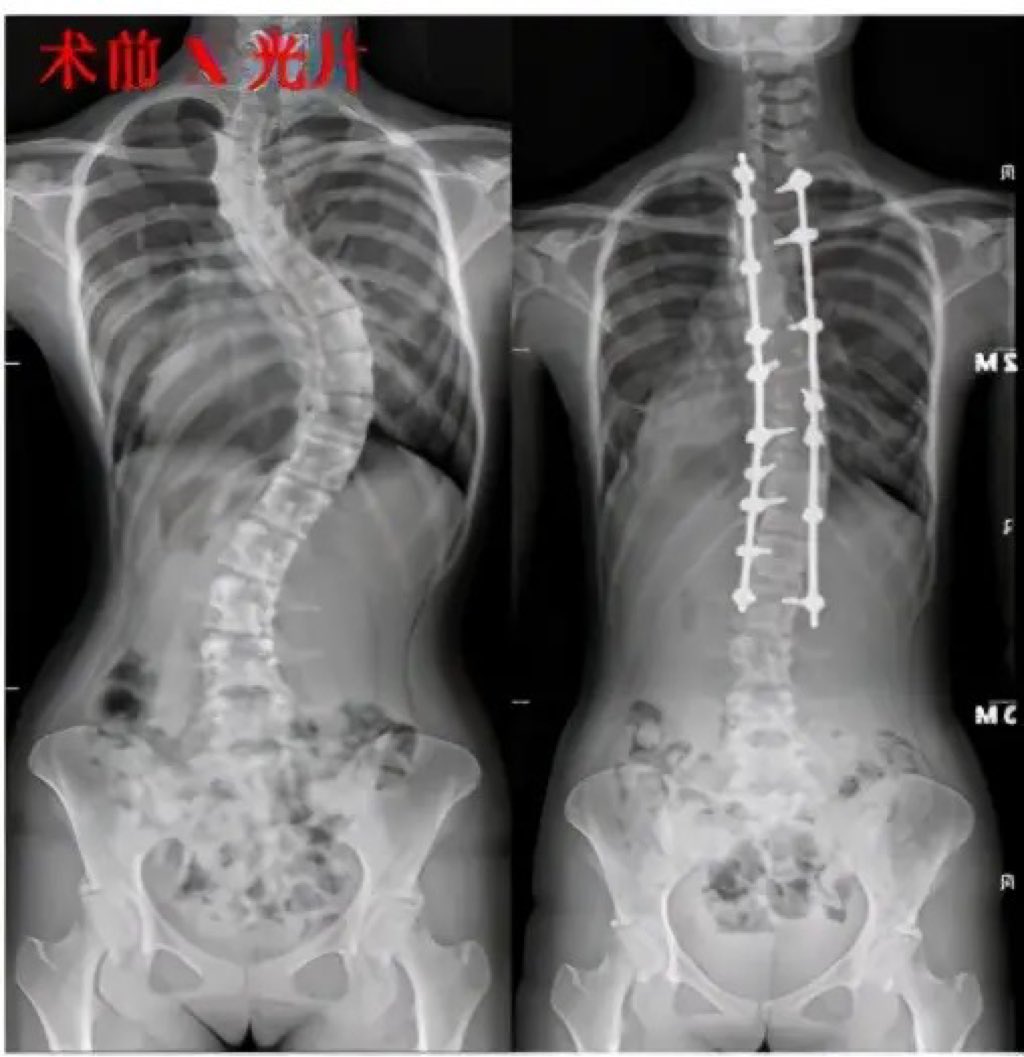

37岁的云南农民李大山蜷缩在转运担架上,他的视线里只有医院走廊的第三块地砖纹路——这是他被强直性脊柱炎折叠28年来,一个能直视的"天空"。术前测量显示,他的脊柱弯曲达162度,胸骨与耻骨间距仅剩8.7厘米。

北京协和医院骨科数据库显示,我国超百万重度脊柱畸形患者中,68%因传统手术风险过高放弃治疗。而2024年6月启用的4D打印椎体置换技术,将手术致瘫率从22%降至1.3%,让"折叠人"挺直脊梁从科幻走向现实。

"就像在脊柱里种下智能脚手架。"主刀医生展示术中影像,12枚人工椎体植入后,以每分钟0.5度的速度同步矫正,既避免瞬间牵拉导致神经断裂,又能动态适应肌肉记忆重建。